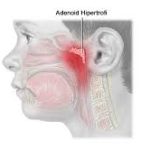

Pediatrik hastada adenoid hipertrofisi (yani adenoid dokusunun normalden fazla büyümesi), orta kulak ventilasyonu üzerinde önemli etkiler yaratır. Bunun temelinde anatomik ve fizyolojik mekanizmalar yatar. Aşağıda adım adım açıklıyorum:

2. Adenoid Hipertrofisinin Mekanik Etkisi

Adenoid dokusu nasofarenkste, Östaki borusunun açıldığı bölgeye yakın bulunur.

Adenoid hipertrofisi durumunda:

Östaki borusunun farengeal açıklığı direkt olarak mekanik olarak tıkanır.

Bu tıkanma, orta kulakta negatif basınç oluşmasına ve sıvı birikmesine (otitis media effüzyon) yol açar.